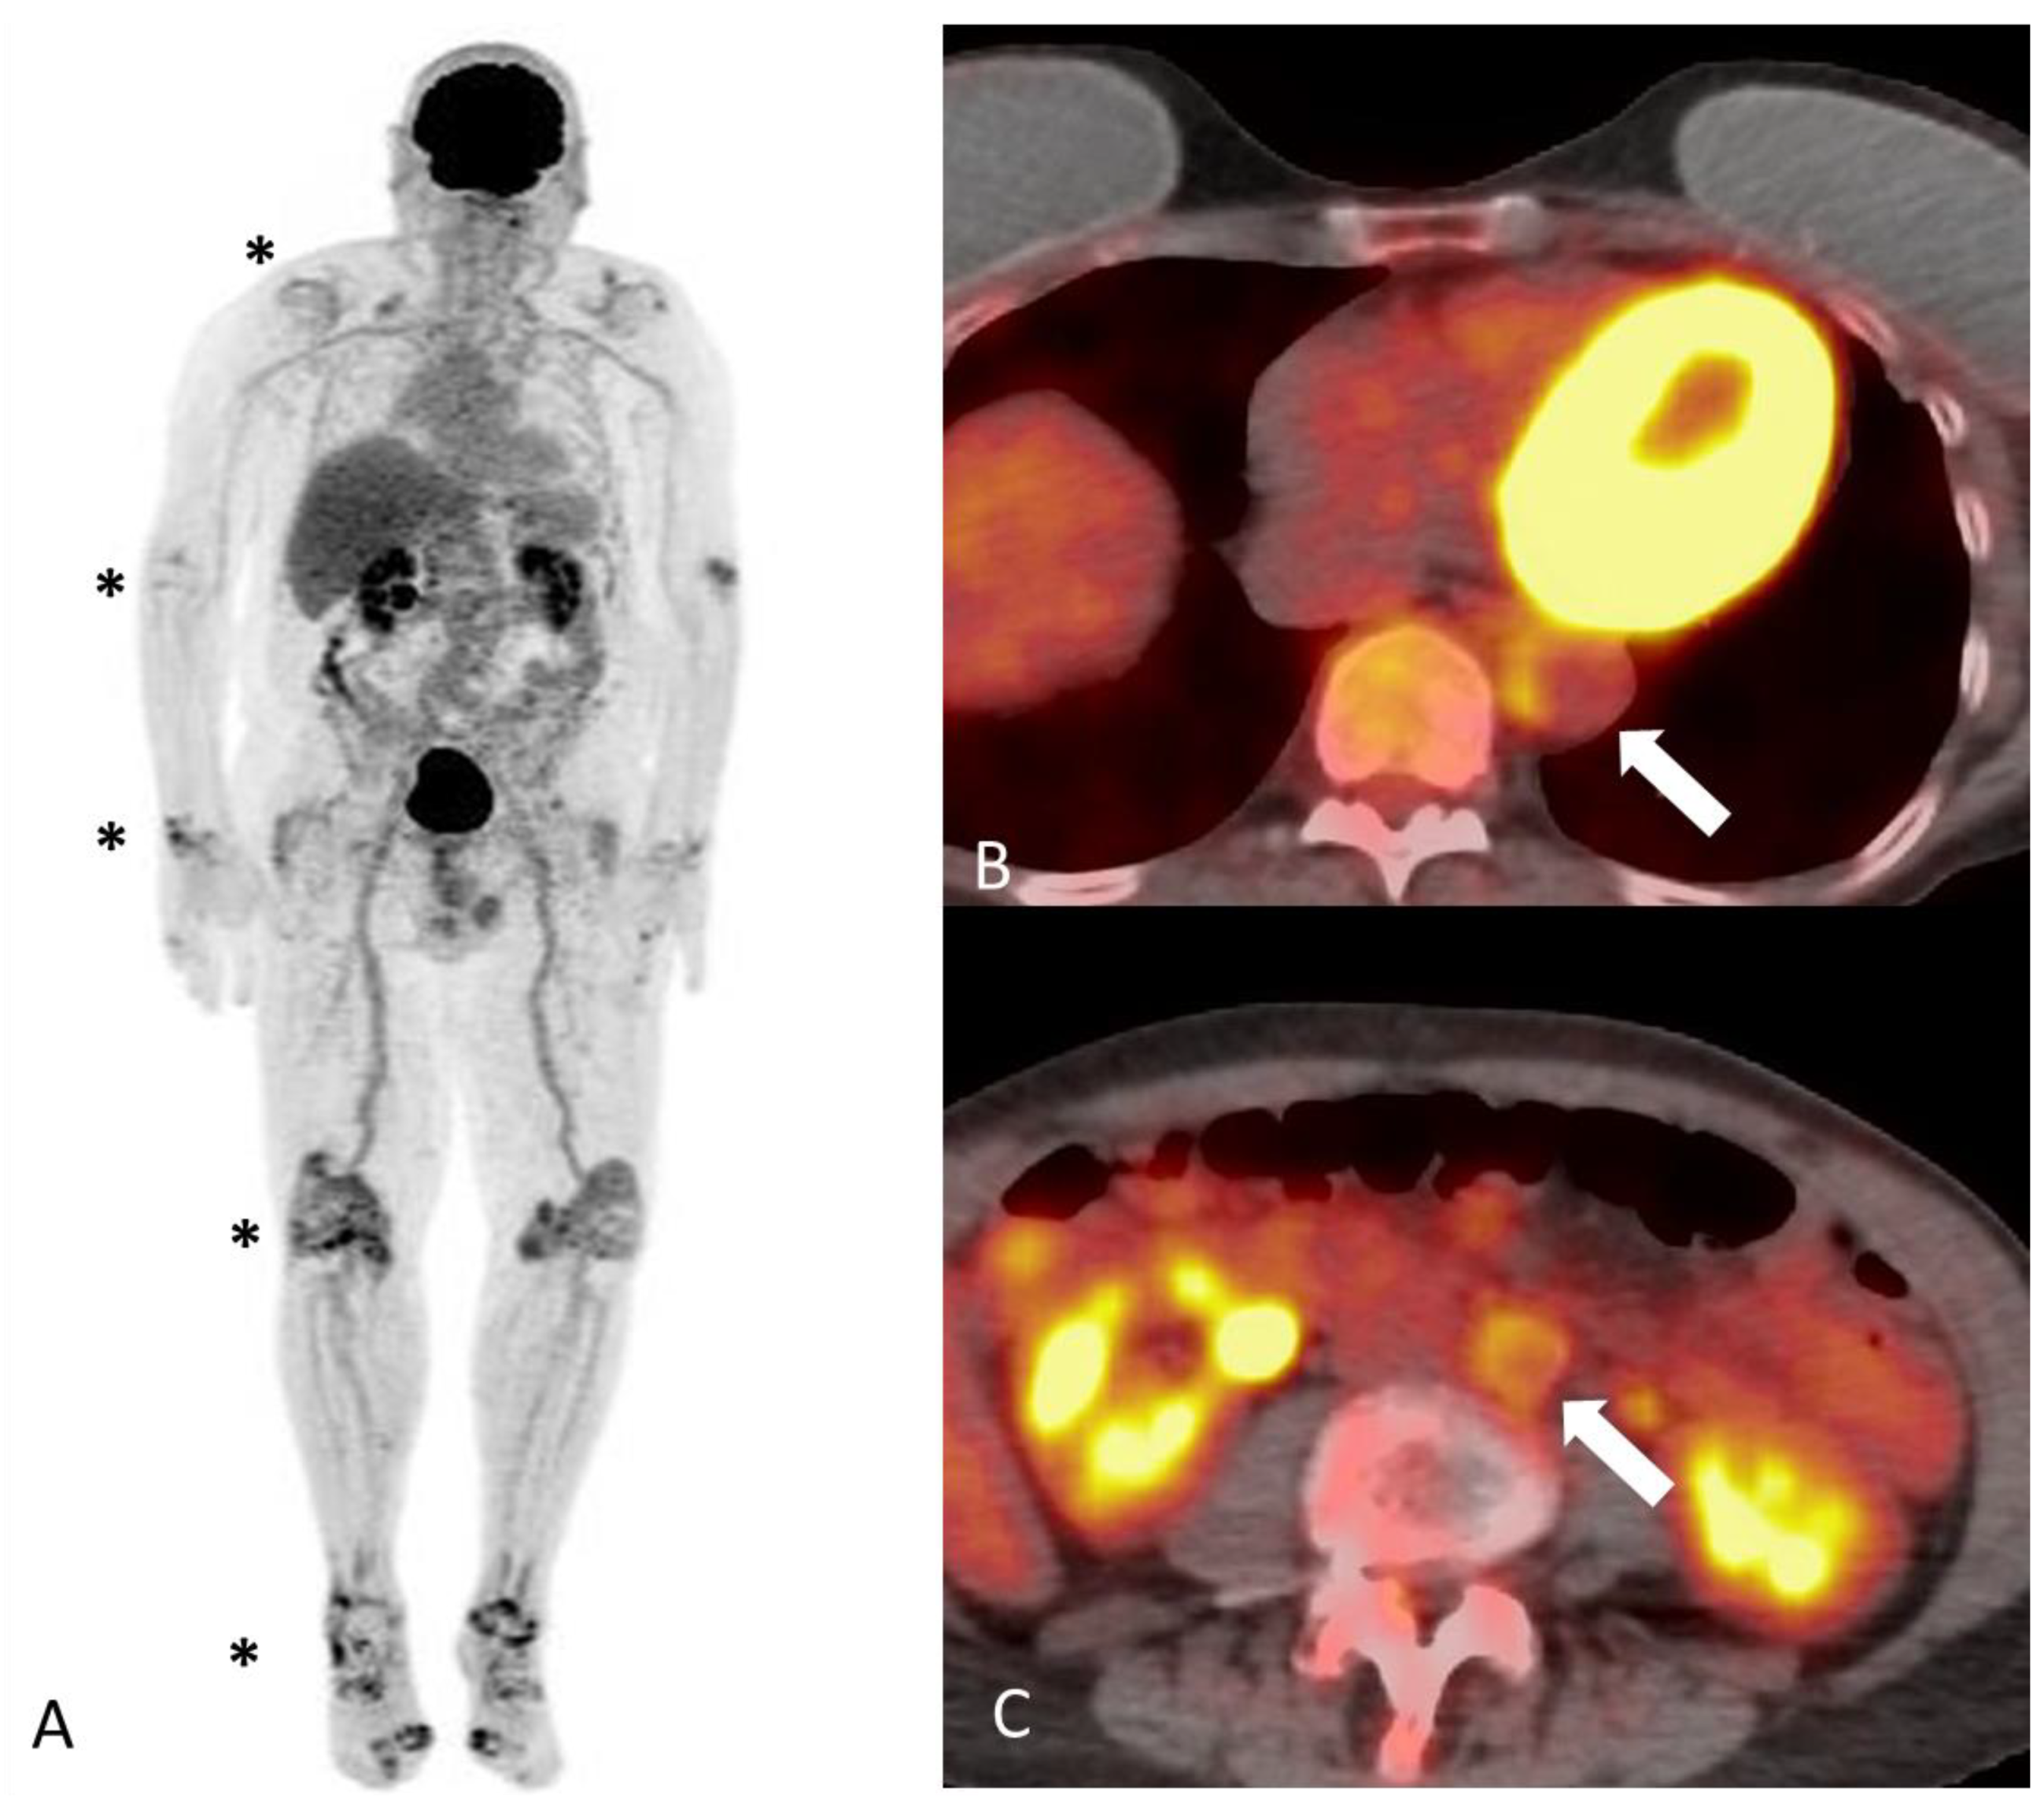

2.2.1. Polyarteritis Nodosa

2.2.2. Kawasaki Disease